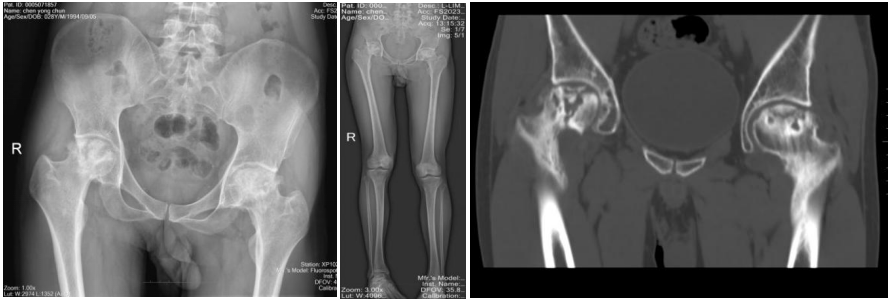

刚入院时,患者在进行主动活动时,双侧髋关节疼痛剧烈,感到十分痛苦。查体可见其双下肢不等长,右下肢较左下肢短缩约3cm,双侧髋关节被动活动时可感受到明显的抵抗。袁勇专家团队接诊后,立即完善了X线、CT及核磁等检查,发现患者双侧股骨头已缺血性坏死,并且因常年的磨损已导致双侧髋关节骨性关节炎的发生,股骨头骨质增生、硬化,致双侧髋关节僵硬

由于患者年仅28岁,全髋关节置换是髋部疾患的终末治疗手段,是否为如此年轻的患者施行手术?是对一侧髋关节还是双侧髋关节同时施行手术?急诊外科全体医护人员高度重视,袁勇专家团队详尽地讨论了手术的方案,最终决定通过一次手术帮助患者完成双侧的髋关节置换,同时要纠正患者双下肢不等长的畸形。

患者术后复查双侧髋关节假体位置良好,双下肢已恢复到同一长度,得以重新自由地行走。此次手术的顺利完成,充分体现了急诊医学部急诊外科医护团队积极探索,勇于创新的进取精神,更展示了对待患者病痛时的细心、耐心和专业的诊疗水平。今后,急诊医学部急诊外科将不断探索和学习,优化诊疗流程,为人民群众的生命健康、生存质量继续保驾护航。